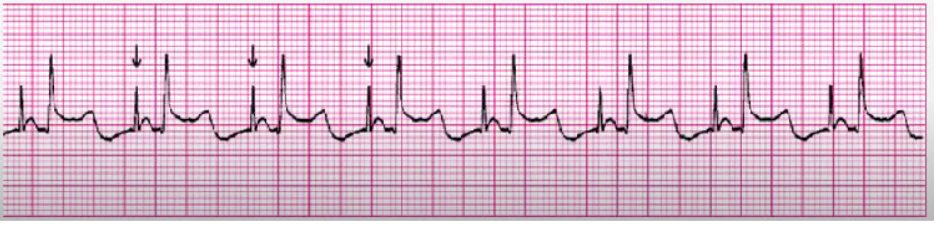

NSR with PACs

treat underlying cause if sx

BBs, Ca Channel Blockers, anti-anxiety meds

monitor someone with LOTS of PACs, could turn into atrial dysrhythmia

<p>treat underlying cause if sx</p><p>BBs, Ca Channel Blockers, anti-anxiety meds</p><p>monitor someone with LOTS of PACs, could turn into atrial dysrhythmia</p>